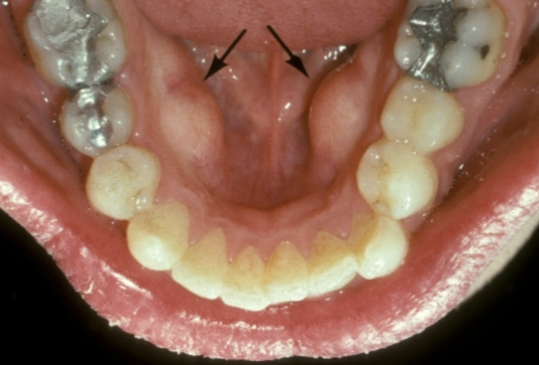

outgrowths of normal dense bone found on the lingual aspect of the mandible premolars are

mandibular tori